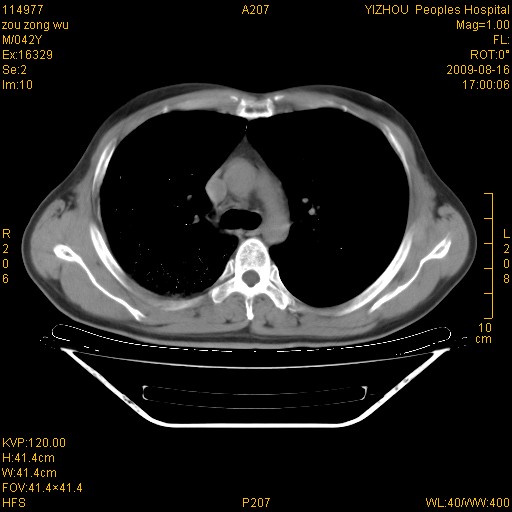

以下是引用zjzjr在2009-8-17 10:42:00的发言:[br]右侧间质性肺炎伴纤维化,右肺下叶肺囊肿伴感染(不除外外伤后引起),右肺野及胸壁软组织\\肝内见多发斑点状,中枪了吧.右侧胸膜肥厚\\粘连.